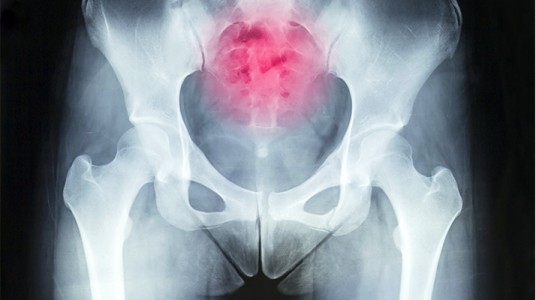

الأورام في منطقة العصعص

وهذه أحد الأسباب النادرة لحدوث الآلام في منطقة العصعص.

والأورام قد تكون أوراما حميدة أو غير حميدة تنتج في العظام التي تكوّن الجزء السفلي من منطقة العمود الفقري المعروفة باسم (sacrum).

وعلى الرغم من ندرة هذه الأورام إلا أنها تحدث، ويجب الشك في حدوثها عندما تكون آلام العصعص مزمنة وتزداد مع مرور الوقت، وعندما تصبح مزعجة أثناء الراحة وأثناء النوم، وعندما لا تستجيب للعلاجات التي ذكرناها سابقاً.

وفي هذه الحالات يجب عمل أشعة رنين مغناطيسي وأشعة مقطعية وأشعة سينية لمنطقة أسفل العمود الفقري التي تقع حول العصعص لتشخيص هذه الحالات وعلاجها مبكراً.

وفي حال حدوث هذه الأورام فإن العلاج يكون تحت إشراف طاقم طبي متكامل يتكون من استشاري الأورام واستشاري الجراحة العامة واستشاري جراحة العظام.

وعند اكتشافها مبكراً فإن هذه الحالات يمكن القضاء عليها وإزالة المرض بشكل كامل.